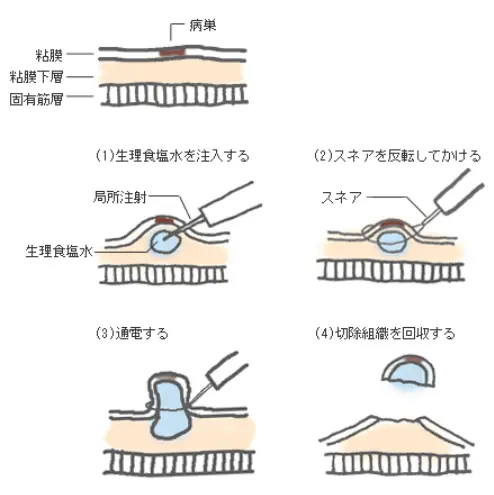

「スネア」と呼ばれる金属の輪でポリープの根元を縛り、電気を流して切除します。日帰りで行える有用な治療法ですが、大きさや形状によってはスネアで切除出来ません。その場合は、ESD(内視鏡的粘膜下層剥離術)が必要になります。

ポリペクトミー、EMR (内視鏡的粘膜切除術)

長所:多くの場合、日帰りで治療出来る。

短所:大きな病変は切除出来ない(目安は2cm程度まで)。

<EMRの手順>(※ポリペクトミーはEMRの手順から生理食塩水の注入を省略する)。